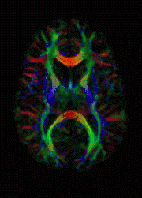

| Diffusion tensor | DTI | Mainly tractography (pictured) by an overall greater Brownian motion of water molecules in the directions of nerve fibers.[21] |

The recent development of diffusion tensor imaging (DTI)[43] enables diffusion to be measured in multiple directions, and the fractional anisotropy in each direction to be calculated for each voxel. This enables researchers to make brain maps of fiber directions to examine the connectivity of different regions in the brain (using tractography) or to examine areas of neural degeneration and demyelination in diseases like multiple sclerosis.